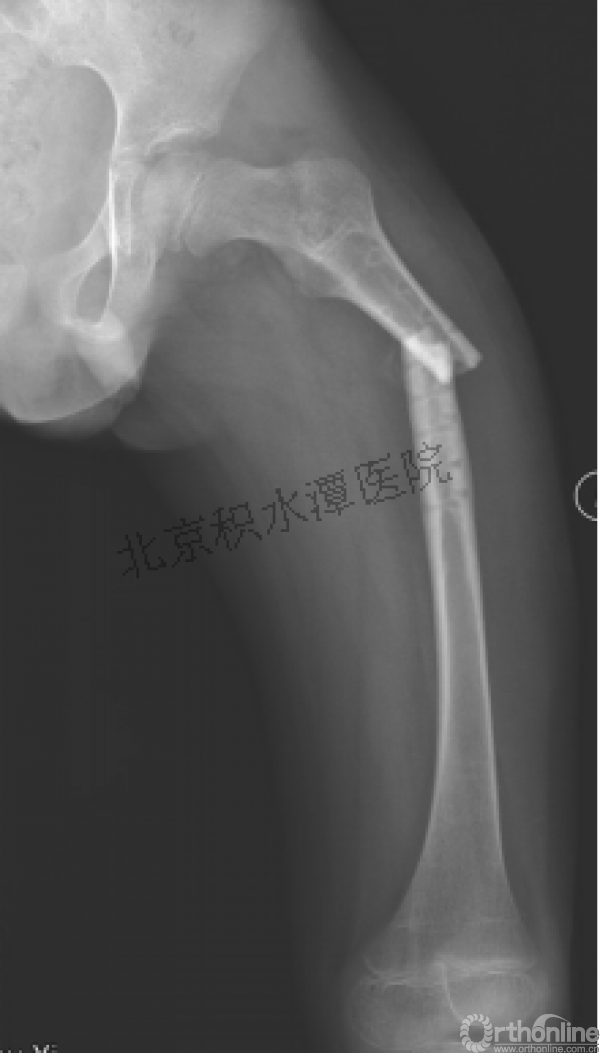

病例分享二

2岁、股骨干骨折,切开+内固定

简单牵引即可!为什么要如此大动干戈?

现实中又是怎样的呢?不知道这属于知识缺乏范畴还是道德品质问题?

匪夷所思!

新生儿股骨干骨折

为什么要手术治疗?

医源性损伤—不愈合!

不具备对儿童骨骼特点的基本了解,不了解儿童骨折的特点,想当然地治疗!